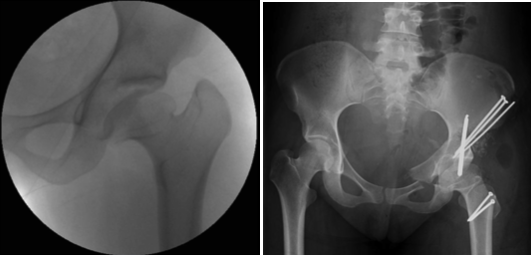

Treatment

Treatment can be selective — identifying and treating the most likely cause of hip pain and dysfunction — or comprehensive, correcting all potential causes in one stage. Dr. Prasad Gourineni performs arthroscopic evaluation and correction of mild asphericity of the head or acetabular retroversion when the remaining morphological variations are mild and unlikely to cause symptoms. In more severe deformities, all abnormalities are corrected with the surgical dislocation approach, which allows head reshaping, neck lengthening, greater trochanter transfer, and acetabuloplasty.